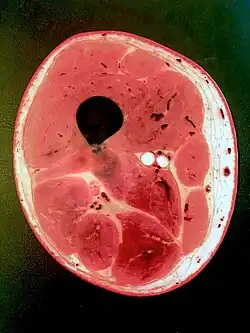

Photo of cross-sectional slice from a plastinated human thigh. -

Schematic drawing of a transverse section of the thigh illustrating its fascial anatomy.